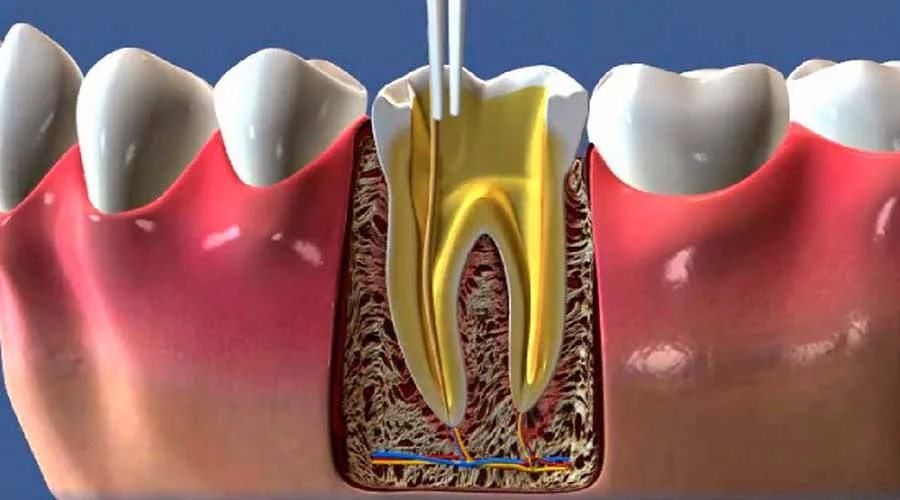

A endodontia envolve a limpeza e desinfecção dos canais radiculares.

Após essa etapa, o dente é obturado com materiais biocompatíveis.

A endodontia é uma especialidade da odontologia que se concentra no tratamento da polpa dentária.

A polpa é a parte interna do dente, rica em nervos e vasos sanguíneos.

Quando essa parte é afetada por infecções ou traumas, o tratamento se torna necessário.

O tratamento de endodontia é realizado em várias etapas.

Após o diagnóstico, o dentista anestesia a área afetada.

Em seguida, ele faz uma abertura no dente para acessar os canais radiculares.

A limpeza é feita com instrumentos específicos, assegurando a remoção de tecidos infectados.

Por fim, os canais são obturados e o dente é restaurado.